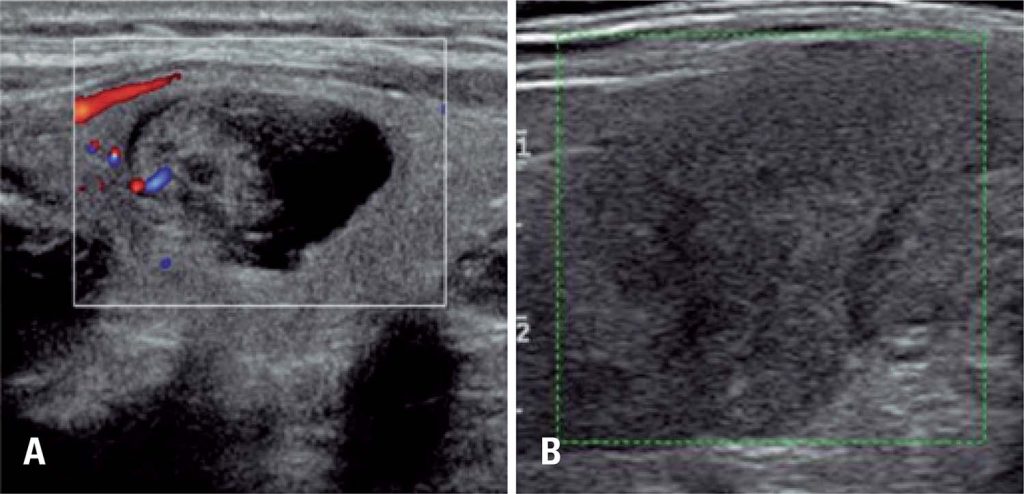

Correlação entre a classificação Thyroid Imaging Reporting and Data System [TI-RADS] e punção aspirativa por agulha fina: experiência com 1.000 nódulos

Apresentar a correlação entre o Thyroid Imaging Reporting and Data System (TI-RADS) e o sistema Bethesda, para relatar citopatologia em 1.000 nódulos tireoidianos.

Estudo retrospectivo realizado no período de novembro de 2011 a fevereiro de 2014, que avaliou 1.000 nódulos tireoidianos de 906 pacientes submetidos a exame de ultrassonografia e à punção aspirativa por agulha fina.

Observou-se associação significativa entre o TI-RADS e o resultado da classificação de Bethesda (p<0,001). A maioria dos indivíduos com TI-RADS 2 ou 3 teve resultado citológico Bethesda 2 (95,5% e 92,5%, respectivamente). Entre aqueles classificados TI-RADS 4C e 5, a maioria teve resultado Bethesda 6 (68,2% e 91,3%, respectivamente; p<0,001). A proporção de malignidades em TI-RADS 2 foi 0,8% e em TI-RADS 3 foi 1,7%. Entre TI-RADS 4A, foi de 16,0%, 43,2% em 4B, 72,7% em 4C e em 5 foi de 91,3% (p<0,001), mostrando clara associação entre o TI-RADS e os resultados da biópsia.

O TI-RADS é apropriado para avaliar nódulos da tireoide e evitar punção aspirativa por agulha fina desnecessária, além de auxiliar na decisão sobre quando este procedimento deve ser realizado.